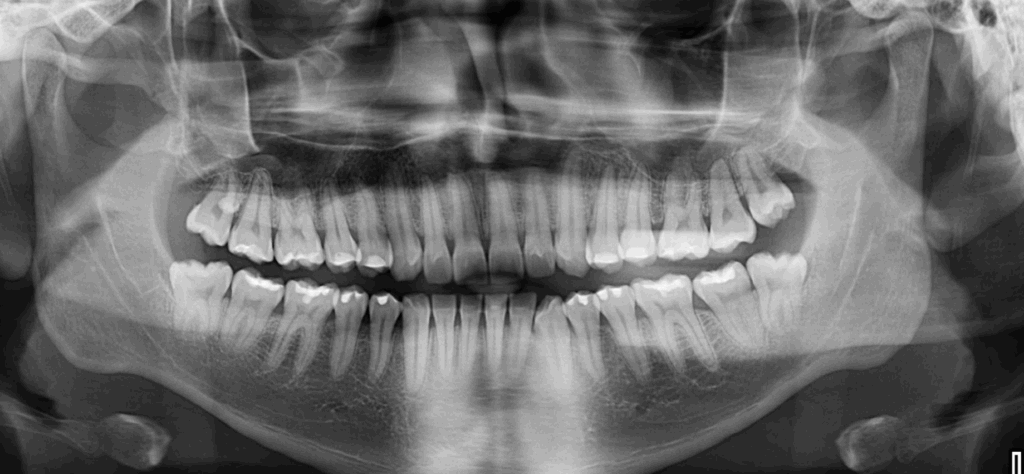

Paciente masculino de 25 años de edad acude al Instituto para una tomografía de macizo facial para la colocación de ortodoncia, a la evaluación de la radiografía panorámica se observa la neumatización de ambos senos

maxilares, atrición de piezas dentarias anterosuperiores y anteroinferiores, múltiples restauraciones coronarias, la retención de las piezas dentarias 38 y 48, ambas en relación con el borde anterior de la rama mandibular. Además, llama la atención una imagen radiopaca de forma redondeada proyectada sobre la porción radicular de la pieza 17.

Radiografia Panorámica